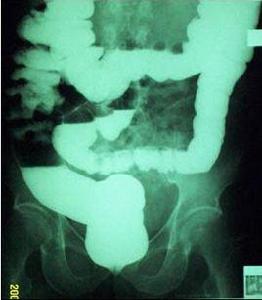

無力性便秘患者排便次數減少後,糞便呈 油灰狀。直腸檢查能夠發現其壺腹部充滿糞便,但患者卻無便意,而且即使用力也不能有效地排便。如果用造影劑顯影,就會發現其結腸不僅變長而且容積也有所擴大。